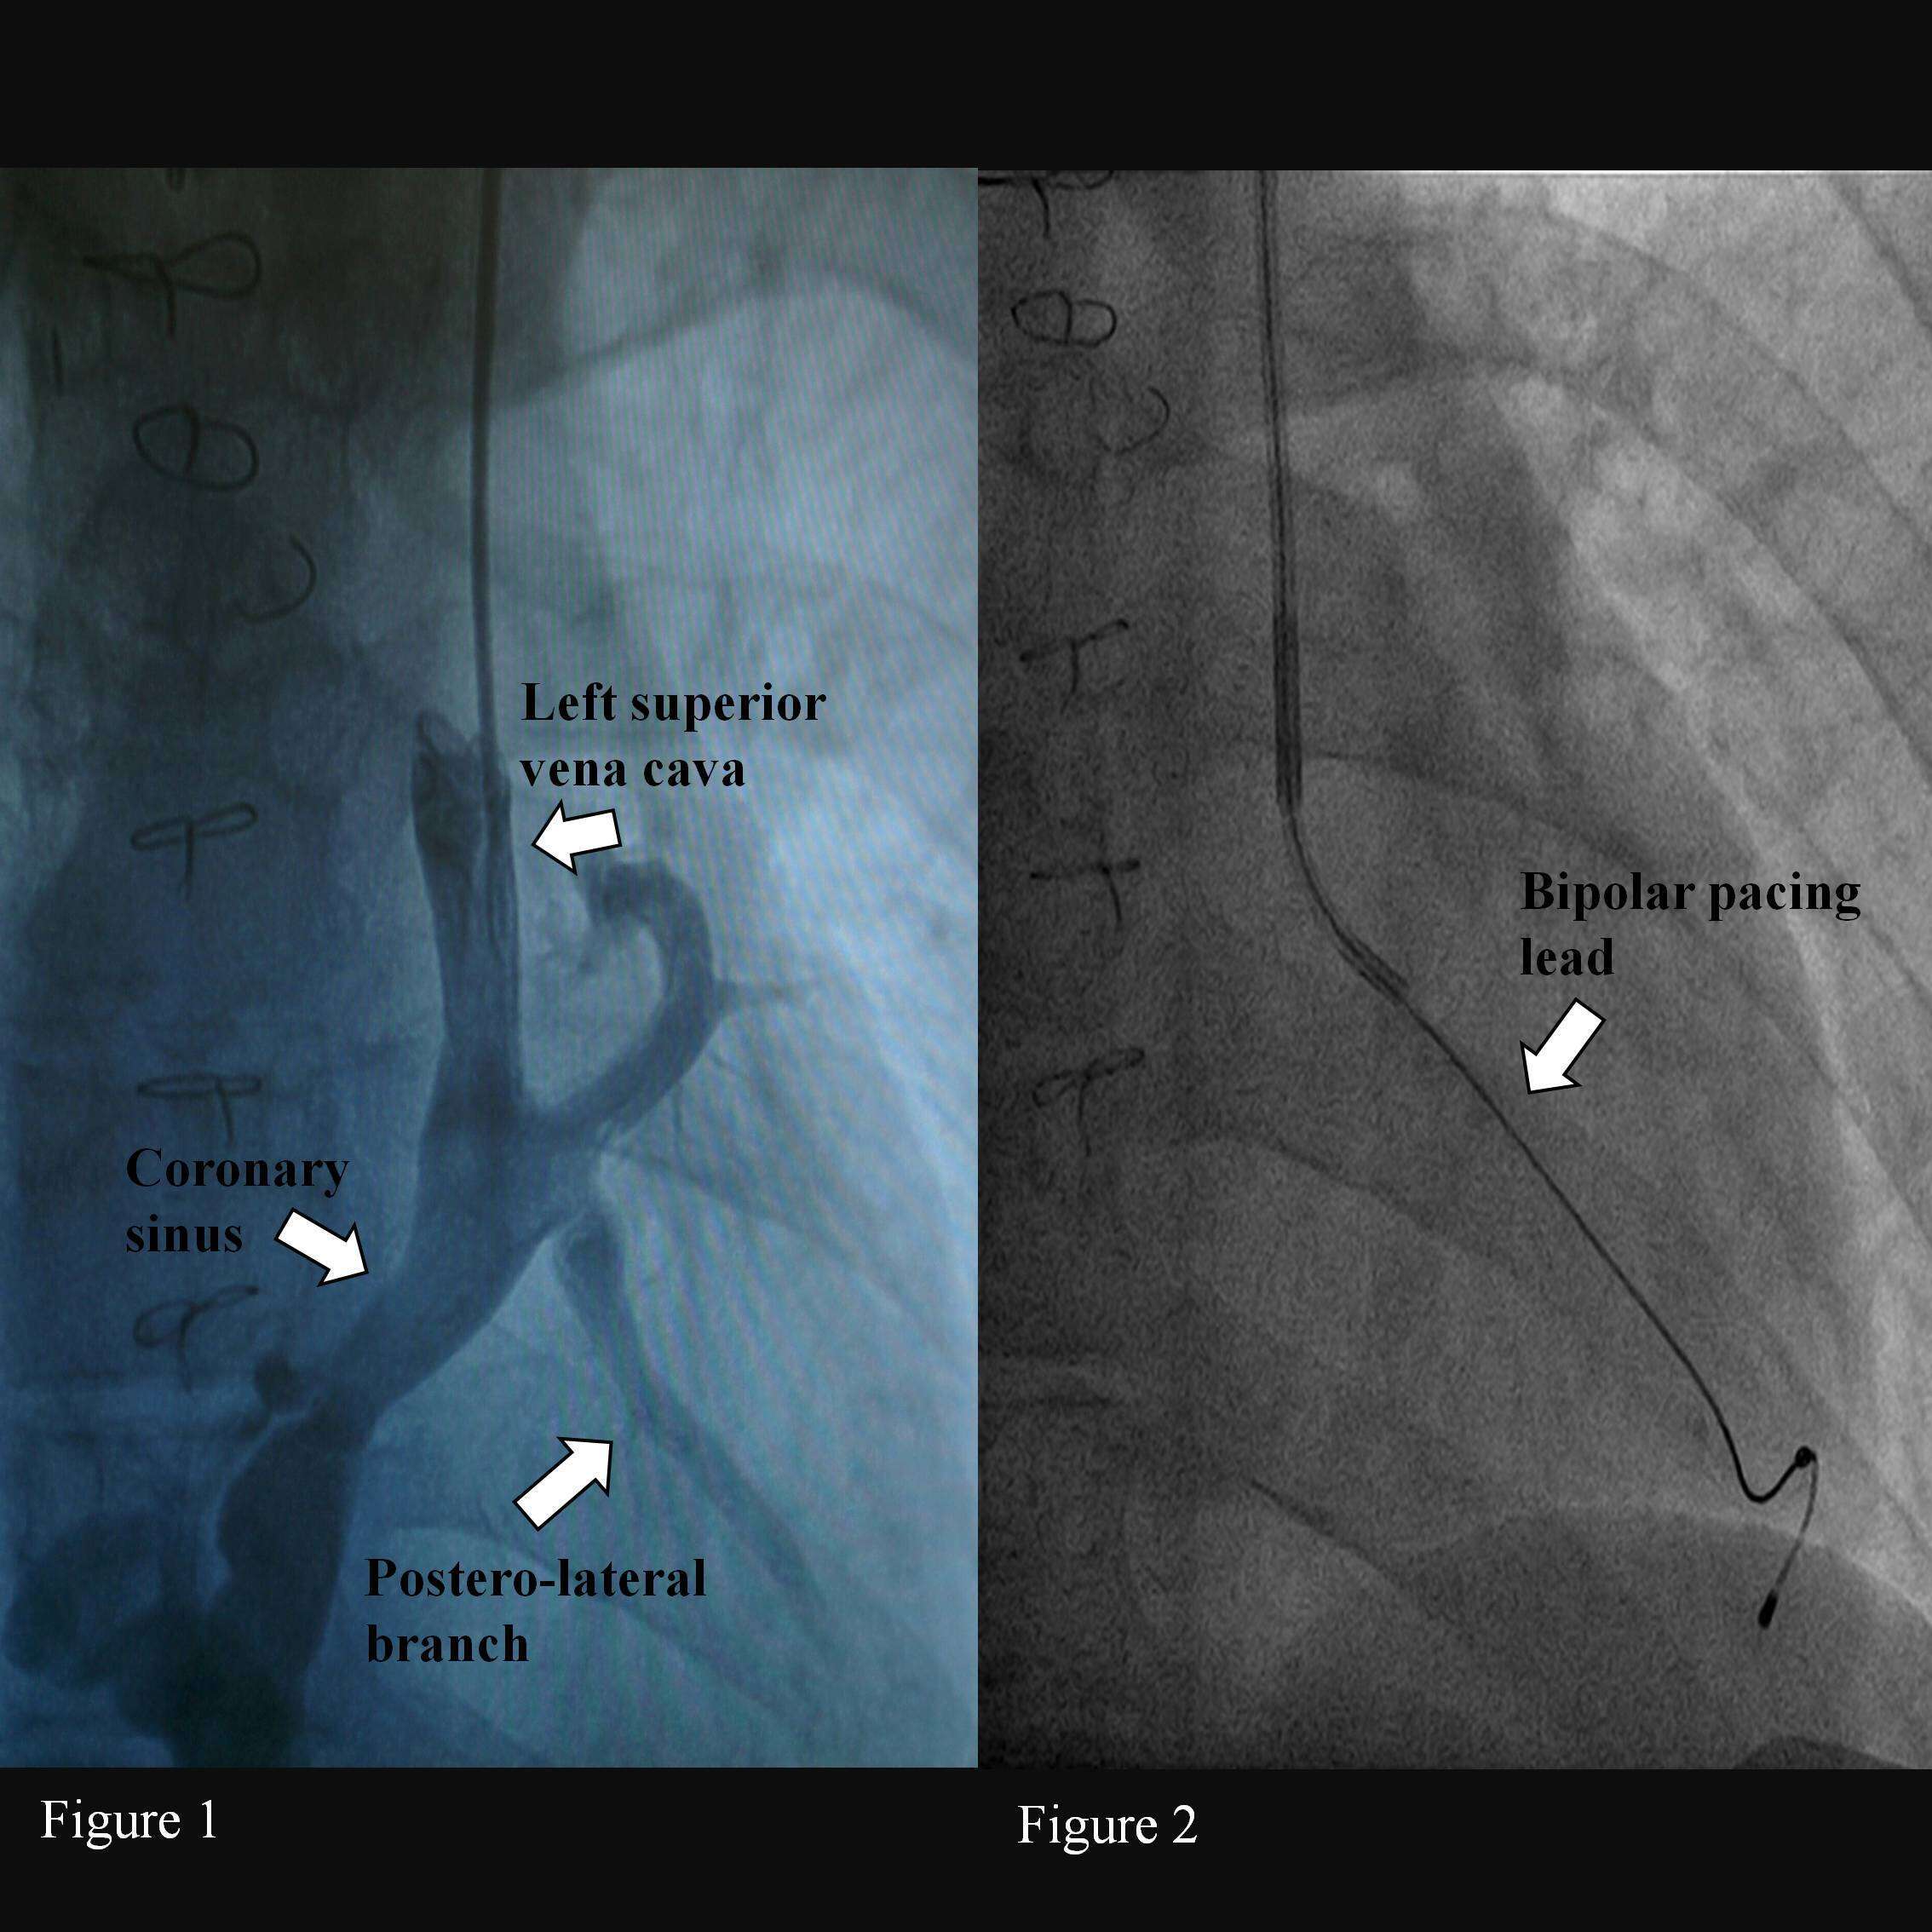

Pacemaker implantation. After left axillary vein puncture a guide was inserted in the LSVC. Through a peel-away 9 Fr introducer an angiography was performed. The angiography showed the presence of a wide CS with a postero-lateral collateral straight on (fig.1). A CRT sub-selection catheter was introduce in the ostium of the

CS collateral. A CRT Bipolar lead was positioned in a distal branch of the vein (Medtronic ATTAIN ABILITY™ 4296 ) (fig. 2). No complication occurred. After 3 months the lead showed normal electrical values and low threshold (1 V/0,4 ms).